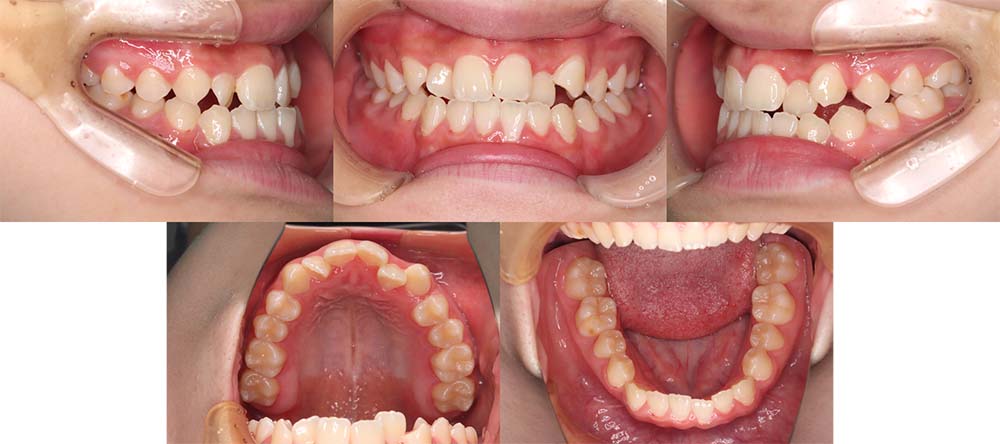

| 症例分類 | 顎変形症、叢生、側方偏移 |

| 診断名 | 下顎右側偏移を伴う上下叢生 |

| 主訴 | 歯並びがガタガタ、顎が右にずれている |

|---|---|

| 年齢 | 25歳4ヶ月 |

| 性別 | 女性 |

| 抜歯部位 | 上の左右第一小臼歯 |

| 使用装置 | 表側のワイヤー装置+外科矯正(手術を併用した治療) |

| 治療期間 | 2年1ヶ月 |

| 保定装置 | 固定式保定装置、取り外し式保定装置(8時間) |

| 費用 |

保険適応 [検査・診断等] 2万円程度 [装置装着] 5〜7万円程度 [調整料] 2,000〜7,000円程度/回 [手術前検査等] 2万円程度 [保定装置等] 4万円程度 合計18〜25万円程度 |

下顎の右側に偏移があり、骨格的にも受け口だったため、上顎両側第一小臼歯を抜去して、上下顎の手術を併用して治療を行いました。術前は前歯が反対のかみ合わせになり、初診時より咬合、顔貌は一旦悪くなります。術前矯正を1年7ヶ月した後に手術を行いました。

術後の顎間ゴムをしっかりと使用していただけたため、術後7ヶ月で治療が終了することができました。また、顎の歪みが残っていたため矯正治療終了後におとがい形成術をして、下顎の偏移を改善しました。

顎の歪みも下顎の前方感も改善することができ、上下のかみ合わせもしっかりと咬合することができました。